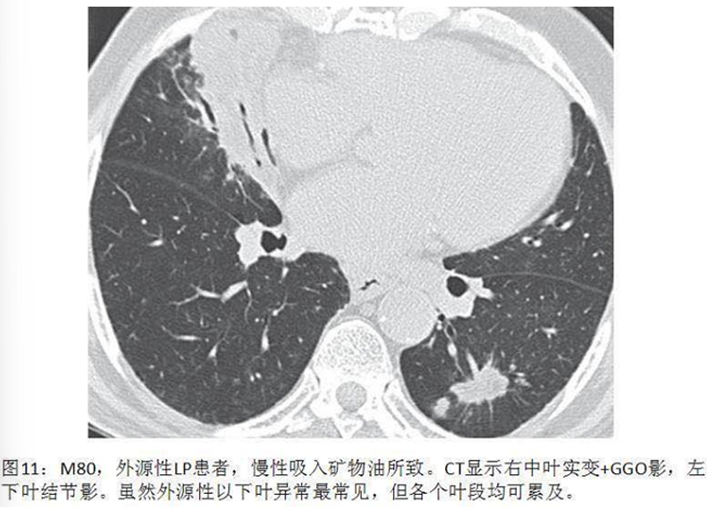

脂质性肺炎被认为由肺泡内含脂物质异物反应所致,脂质到达肺泡的机制:摄入(非挥发烃类)或吸入(挥发烃类),少数矿物油如汽油,即使经静脉注射也可导致肺损伤。在肺泡内,油脂乳化后被巨噬细胞吞噬,肺泡巨噬细胞不能代谢脂肪物质,当巨噬细胞死亡后油脂反复进入肺泡;油脂异常释放导致巨噬细胞肉芽肿反应、慢性炎症反应、肺泡及间隔纤维化;新鲜病灶显示肺泡被载脂巨噬细胞浸润,肺泡壁和间隔基本正常;进展性病灶显示巨大的空泡和肺泡壁、支气管壁和间隔炎性浸润,大量含脂空泡周围纤维化和实质破坏是晚期病变的特征。如果吸入矿物油或植物油,不易在体内分解,易在体内形成结节或肿块。如果吸入动物油,在体内可被分解为脂肪酸,导致炎症反应,局部肺水肿或肺出血。临床表现缺乏特异性,个体差异明显,从无症状到严重,甚至危及生命,常因患者年龄、吸入脂质的时间、数量及种类而不同。有症状的外源性脂质性肺炎常表现为慢性咳嗽或呼吸困难,其他表现为胸痛、咯血、间歇发热等。查体可发现叩诊浊音,听诊可闻及爆破音或干啰音。在长期持续进展性疾病患者中,体检可发现慢性缺氧,如杵状指。外源性类脂性肺炎可模拟许多其他肺部疾病,包括癌、肺炎、急性呼吸窘迫综合征和局部肉芽肿,HRCT最常见的表现是气腔实变、磨玻璃影、铺路石征、小叶间隔增厚、肿块样病变。急性外源性脂质性肺炎一般在吸入后半小时内出现肺部影像异常,大部分患者在24小时内出现肺部阴影,通常呈磨玻璃或实变影,一般在2周至8个月可逐渐改善或吸收,偶尔会遗留少许瘢痕纤维。慢性外源性脂质性肺炎最常见的影像学表现为一个或多个肺段的磨玻璃结节或实变影,通常在支气管周围分布,累及下叶最常见。实变可伴临近肺组织扭曲,在疾病晚期,由于油脂从肺泡内运送至肺间质,可出现增厚的小叶间隔或纤维化,还可见到铺路石征,也可表现为含脂质的结节或肿块影,由于慢性炎症及纤维化,肿块边界常不规则或有毛刺。下图为文献报道的一例急性外源性脂质性肺炎,患者胸部CT主要表现为实变,其中有液化坏死灶。下图为3例外源性脂质性肺炎患者的胸部CT,主要表现为肺结节/肿块和磨玻璃影。治疗3个月后,病变较轻者明显吸收。外源性脂质性肺炎的诊断主要基于暴露史,与疾病相符的影像学改变,唾液、支气管肺泡灌洗液或活检肺组织病理发现富含脂质的巨噬细胞,需要综合以上考虑诊断。支气管肺泡灌洗液的外观有提示价值,常为白色或浑浊液体,在表面可见脂肪漂浮层。